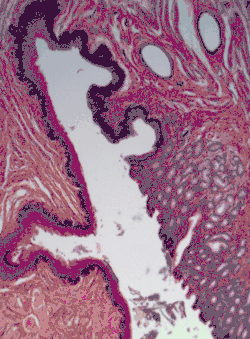

[Micrograph] of normal stratified squamous epithelium and the metaplasic epithelium of Barrett's esophagus (left of image). Alcian blue stain.